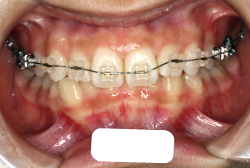

「歯並びの凸凹を直したい」という主訴で来院したケースです。診断の結果、たしかに「叢生」という隙間が足りないと言うことが原因の凸凹症例でした。

しかし、それ以上に問題なのは「前歯の噛み合い方が深すぎる」という症状で、初診の歯の正面写真を見ると下の前歯が全く見えません。こういう症状を矯正学では「過蓋咬合(かがいこうごう)」と言います。過蓋咬合を放置すると、将来的に顎関節に悪影響を与えるとされており、顎関節症の原因因子の一つです。また下の前歯の先端が、上の前歯の裏側の歯茎と強く接触するため、歯周病の原因にもなります。

検査の結果、凸凹が軽症なため非抜歯で矯正すること可能と判断、マルチブラケット装置にて治療しました。治療後は歯並びが綺麗になっただけでなく、噛み合わせ的にも正しい状態が確立しています。